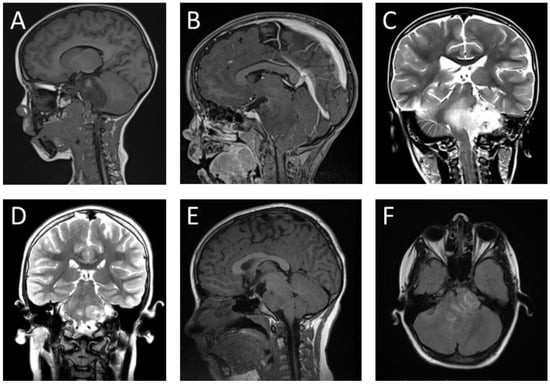

The conventional MRI used for diagnosing DMG typically reveals hypointense signals on T1-weighted images and hyperintense signals on T2-weighted images, without contrast enhancement (Figure 2). This characteristic distinguishes DMG from other brain stem tumors. The tumor frequently localizes in the brain stem pons, occupying more than two-thirds of the total volume of the pons and sometimes extending to surrounding areas [23,26]. Enhancement techniques for imaging vary based on the tumor type and have not been standardized for cases with specific mutations [23].

Some of the most common macroscopic findings on imaging techniques for DMG include necrosis in one in five cases, growth from the cephalocaudal direction towards the midbrain, cerebral peduncles, cerebellum or medulla oblongata, and poorly defined margins [10,26].

These tumors are usually exophytic, solid, and outgrowing, compressing the basilar artery, with rare involvement of the meninges [6,26]. Spectroscopy may show significantly higher choline/N-acetylaspartate and creatine/choline ratios compared to other tumors. Contrast MRI is used after radiotherapy, as radiation necrosis favors contrast uptake [19,26].